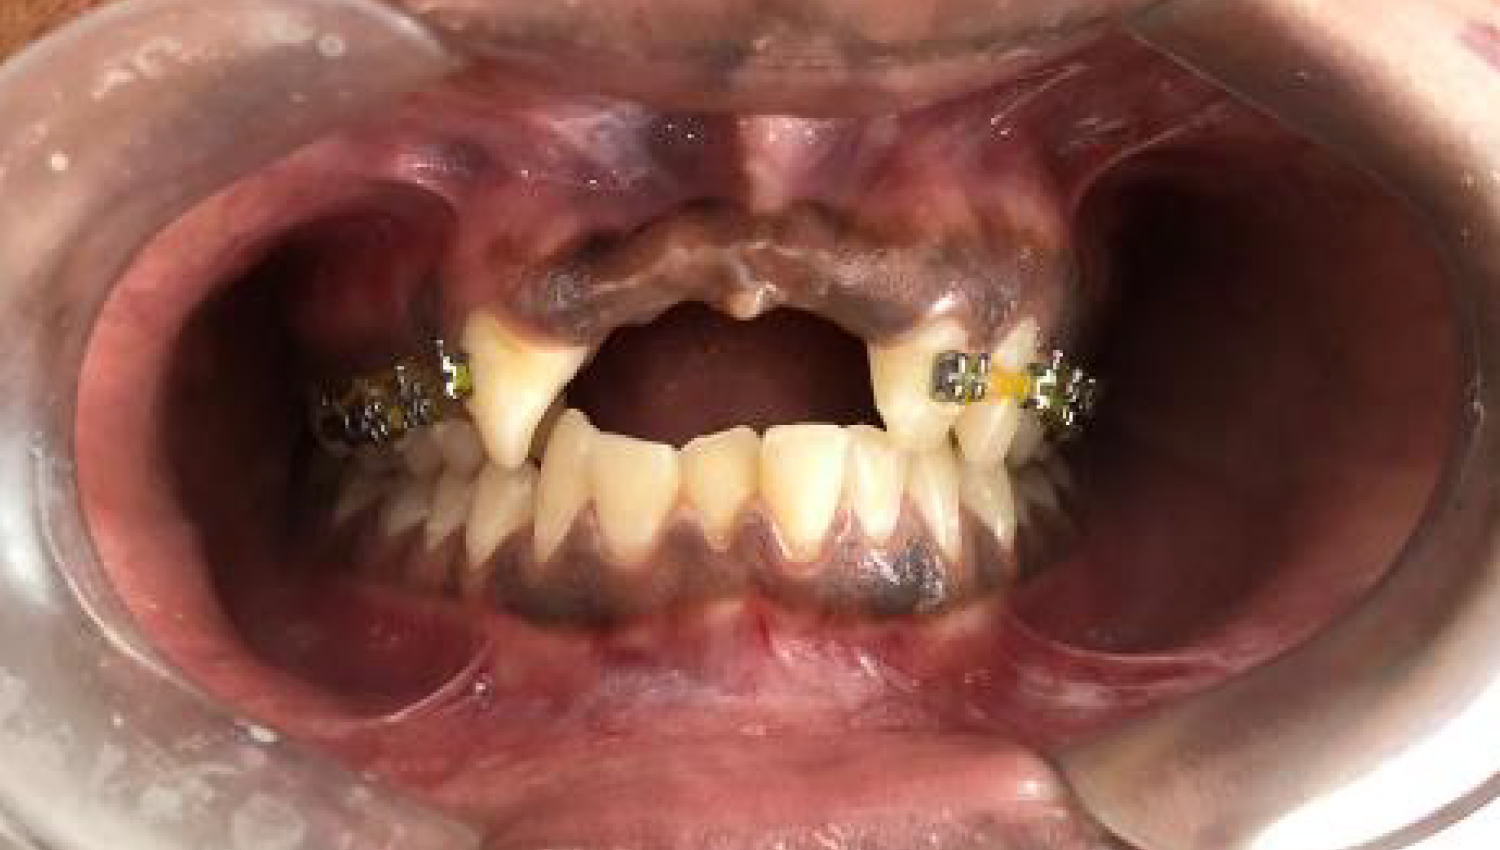

- Male, 30 years old.

- Case performed by Dr. K Pavan Kumar

1.Initial clinical view.